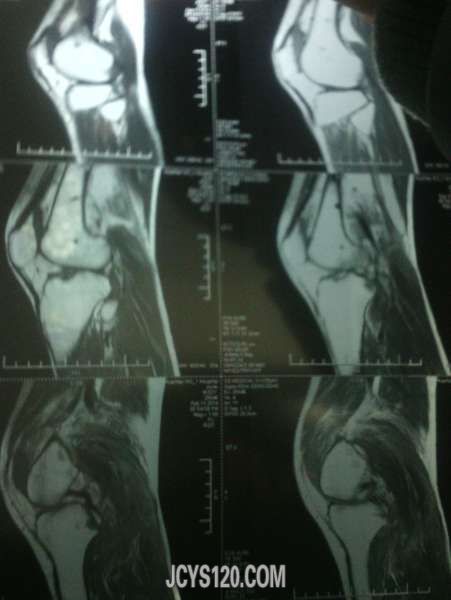

患者33岁男 因路滑扭伤!随即到医院检查,一般情况尚可,右侧膝关节。小腿腹部肿胀疼痛,磁共振影像如下,手机拍摄不是那么清楚!愿个为同行给点建议!需要做关节腔镜手术吗?有没有什么处理的方法给说说!!!

这种核磁影像不是熟悉,希望影像版版主给看看,或者楼主干脆把报告单一并发上来!

谷维素 发表于 2014-2-12 18:44 static/image/common/back.gif 这种核磁影像不是熟悉,希望影像版版主给看看,或者楼主干脆把报告单一并发上来! 谢谢回复!我也是看不太明白!毕竟见的太少~忘高手赐教!!!!

膝关节外力引起的损伤,较轻是以皮肤肌肉肌腱的损伤,严重时则出现半月板撕裂伤,髌骨的骨折。对于皮肤肌肉肌腱的损伤给予常规治疗即可,当出现半月板撕裂伤时可采取半月板的修补或切除术,这些度需要在关节镜下完成,髌骨骨折一般采用功能位的石膏固定。

体检下前后交叉韧带,侧副韧带有没有损伤,膝关节正侧位X片就够了,小腿后腹部肿明显一般是腓肠肌损伤,检查下跟腱有没有损伤,如果有问题再分别撕裂伤还是断裂伤,按情况相应处理,单肿胀用消炎止痛软胶外敷3-5天就可以了。大医院很多检查浪费。。。

片子看不懂,如果没有其他,肿胀是外伤导致静脉回流不畅所致,静滴几天丹参和七叶皂苷钠好的快些。

片子看不懂,患者没有住院。我们可以小心的给与云南白药,龙血竭胶囊治疗,但要注意观察。